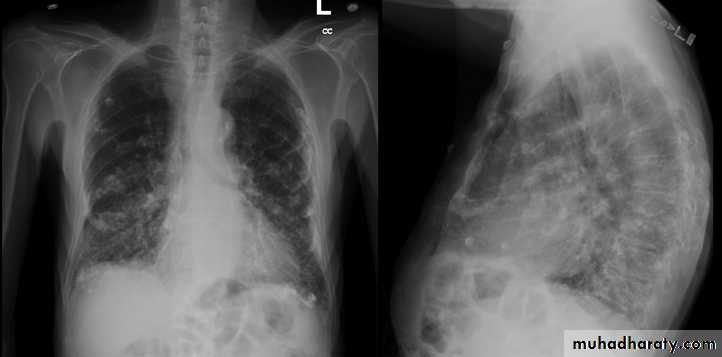

Radiology

Chest X-ray: typically small lung volumes with reticulonodular shadowing

HRCT: reticulonodular shadowing in early stage and honeycomb cysts and traction bronchiectasis in advance stage.

Abnormal chest X-ray at presentation with lower zone bi-basal reticular and reticulonodular opacities. 'honeycomb' appearance in advanced disease.

HRCT may be diagnostic, demonstrating a patchy, predominantly peripheral, subpleural and basal reticular pattern with subpleural cysts (honeycombing).